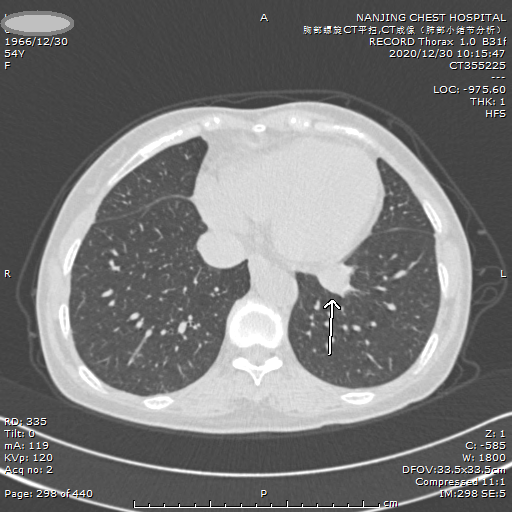

案例一 纯磨玻璃小结节